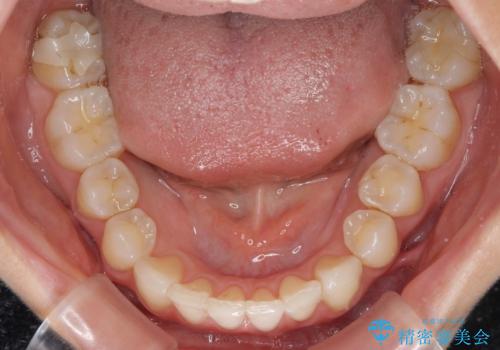

上顎前歯が2本欠損 インビザラインによる叢生の解消

- 深い咬み合わせと前歯のデコボコを気にして来院された患者様です。

上顎前歯2本が欠損しているため、妥協的なゴールを設定しインビザラインで矯正治療を行うこととしました。

上下前歯の大きさのアンバランスにより、深い咬み合わせと奥歯の咬みにくさがなかなか解決されず、治療に長期間を要することとなりました。